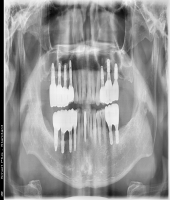

| ● 진료과목 : [임플란트] 틀니 사용중, 임플란트로 교체하기

| ● 내용 : 하악틀니 사용 중 불편감으로 임플란트로 교체한 예 |